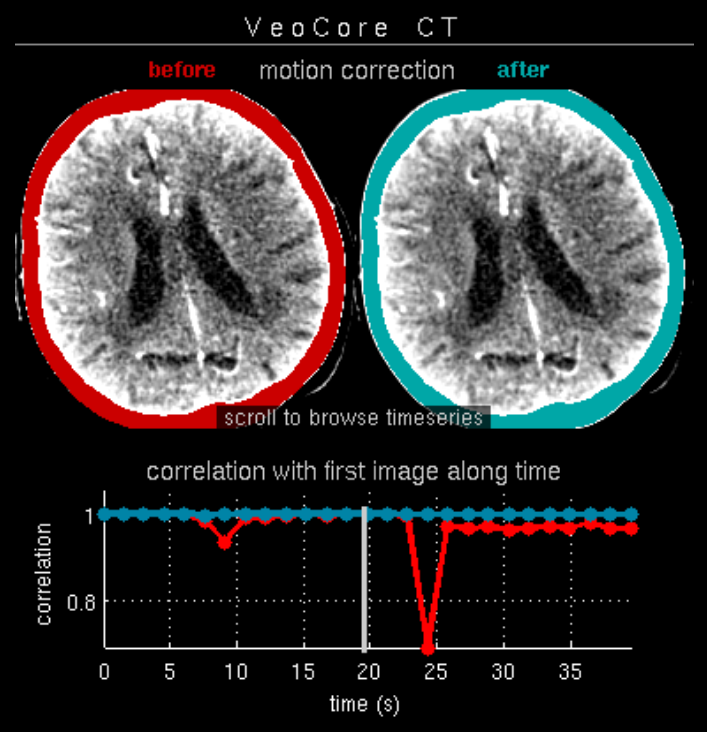

Des Weiteren ist mRay in der Lage eine Verarbeitung von Bildern durchzuführen und so Veränderungen bzw. Anomalien in Geweben zu finden, zu visualisieren und zu quantifizieren. Das Bildverarbeitungsmodul mRay VEOcore kann verwendet werden, um Bilder des Gehirns von Bildgebungsmodalitäten wie CT, Perfusions-CT oder MRT mit diffusionsgewichteter Auswertung (DWI) zu prozessieren. Als Ergebnis werden Kontrastveränderungen über die Zeit als farbige Perfusionskarten angezeigt, dies beinhaltet auch flussbasierte Parameter und Gewebeblutvolumen Berechnungen.

Die Perfusionsanalyse von Aufnahmen des Gehirns ermöglicht die Darstellung und Quantifizierung von minderdurchblutetem Gewebe (Penumbra), nicht-durchblutetem Gewebe (Kerngewebe) und dem Mismatch-Ratio zwischen den beiden Werten. Die berechneten Werte können der Unterstützung bei einer Entscheidungsfindung dienen, die auf der Beurteilung des Ausmaßes der Schädigung von Geweben basiert.